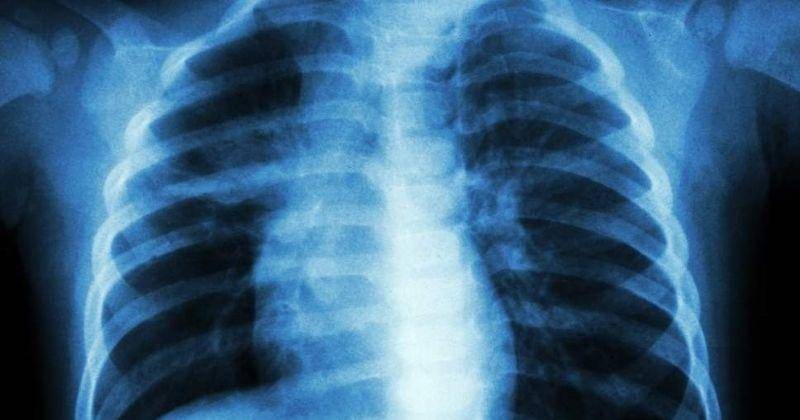

Nah itulah 5 gejala penyakit TB pada anak. Tuberkulosis pada anak biasanya menyerang organ paru-paru meskipun tidak menutup kemungkinan organ lain dapat terserang.